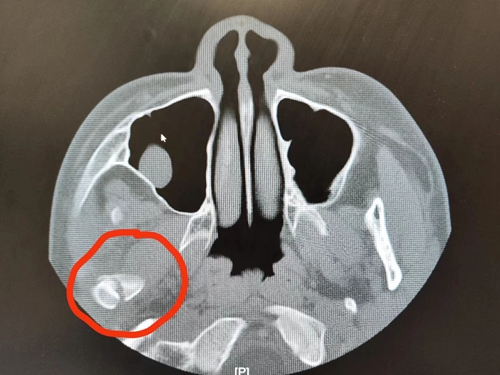

口腔頜面外科接診醫(yī)生立即查看患兒情況,進行CT檢查,沒想到這一摔竟導致麗麗右側(cè)髁狀突骨折。

髁狀突位于顳下頜關(guān)節(jié)窩內(nèi),是下頜骨易發(fā)生骨折的部位之一。髁狀突的損傷會導致張口受限,影響下頜的生長,甚至出現(xiàn)嚴重的面部畸形。

麗麗正處于快速生長發(fā)育期,而髁狀突又是下頜骨發(fā)育的中心之一,處理不當將會嚴重影響后期的咬合關(guān)系與咀嚼功能,影響兒童面部發(fā)育。由于患兒年齡小,骨折位置偏高,接診醫(yī)生決定采用保守治療的方式,通過髁狀突塑形和功能改建,幫助患兒恢復下頜功能。